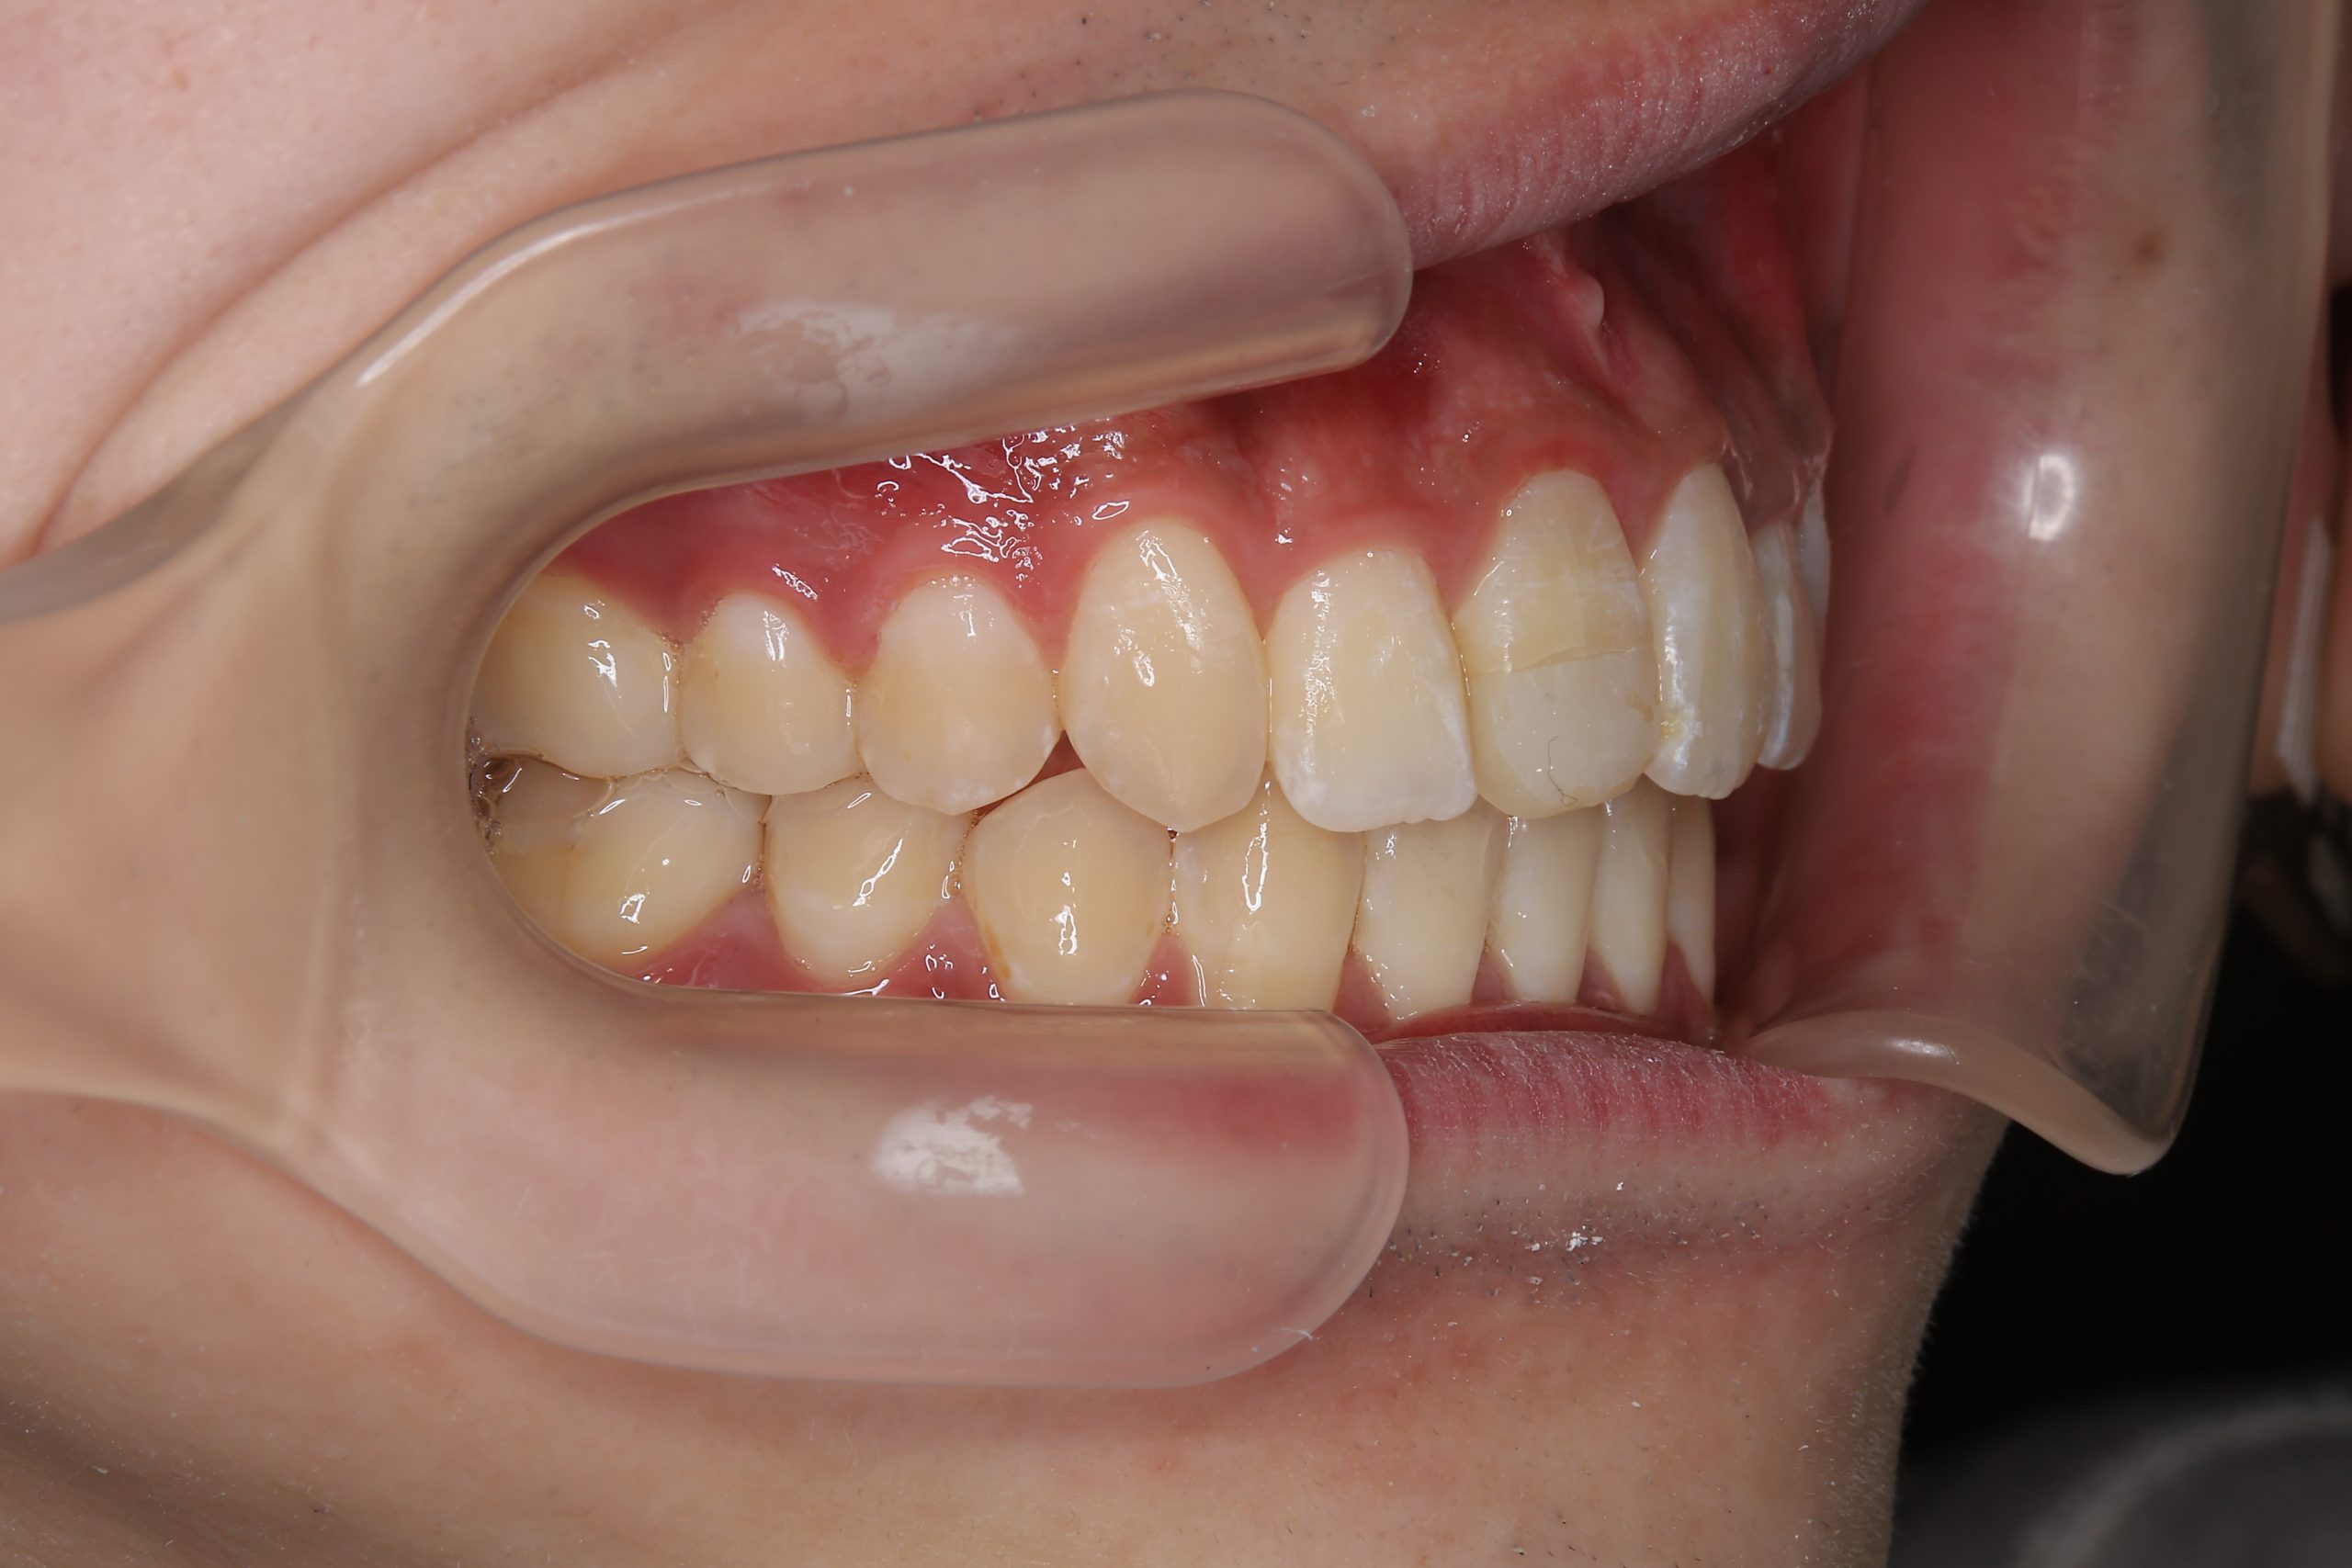

アフター

ワイヤー矯正治療|症例_037

主訴 前歯が少し前に出ている|鼻づまり

施術内容 MSEと下顎リンガルアーチを用いて上下顎骨を拡大した。

その後をマルチブラケット装置を用いて非抜歯で歯牙を配列し、良好な咬合を獲得した。

治癒期間 1年6か月間